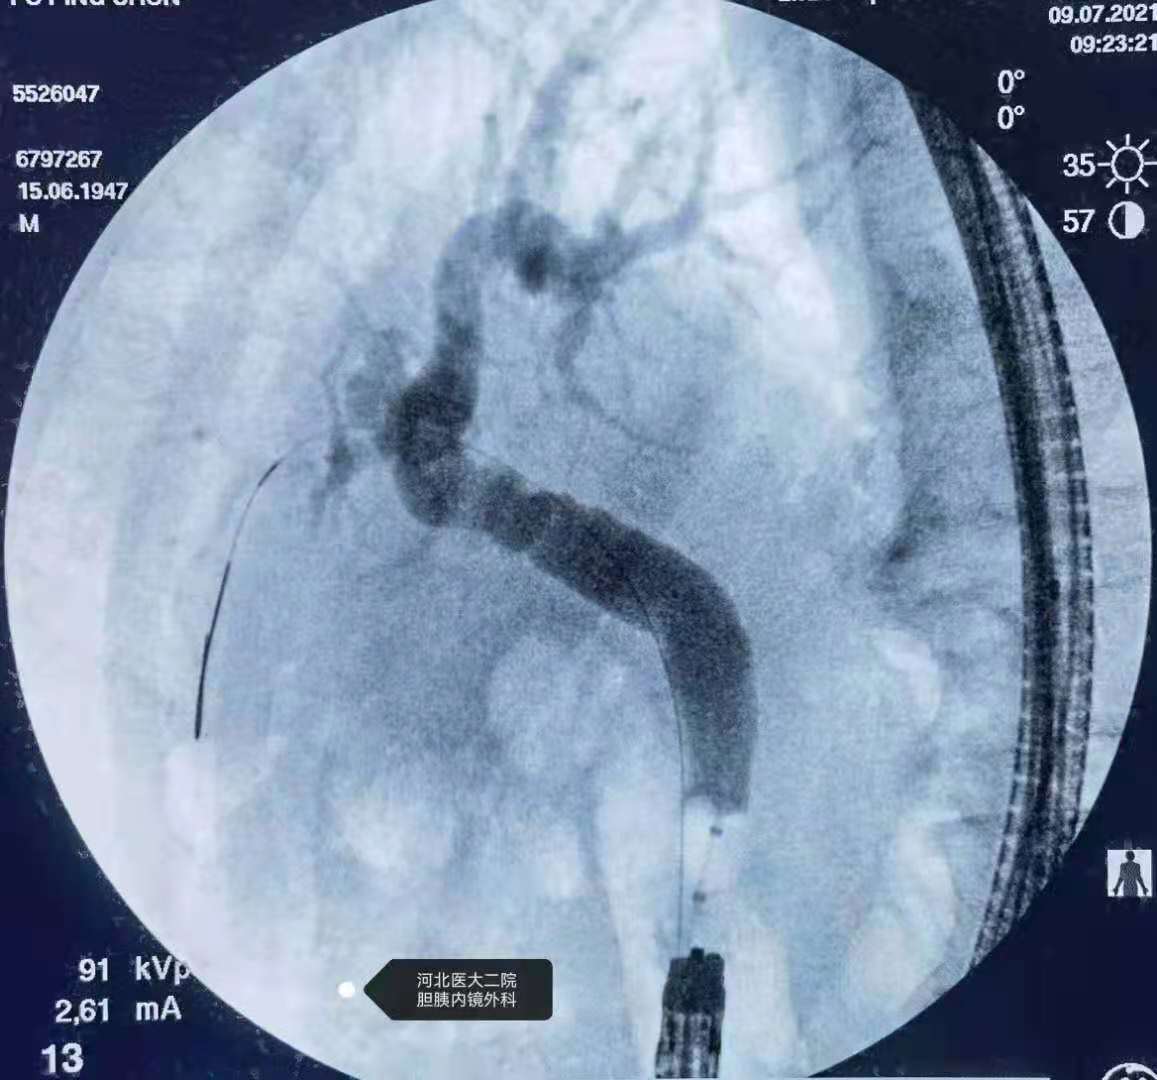

分享一例胃大部切除术后胆总管结石ERCP

上午的一例胃大部切除术后胆总管结石患者。

此类患者我们习惯应用胃镜+透明帽。

取石。

球囊造影。

鼻胆管。